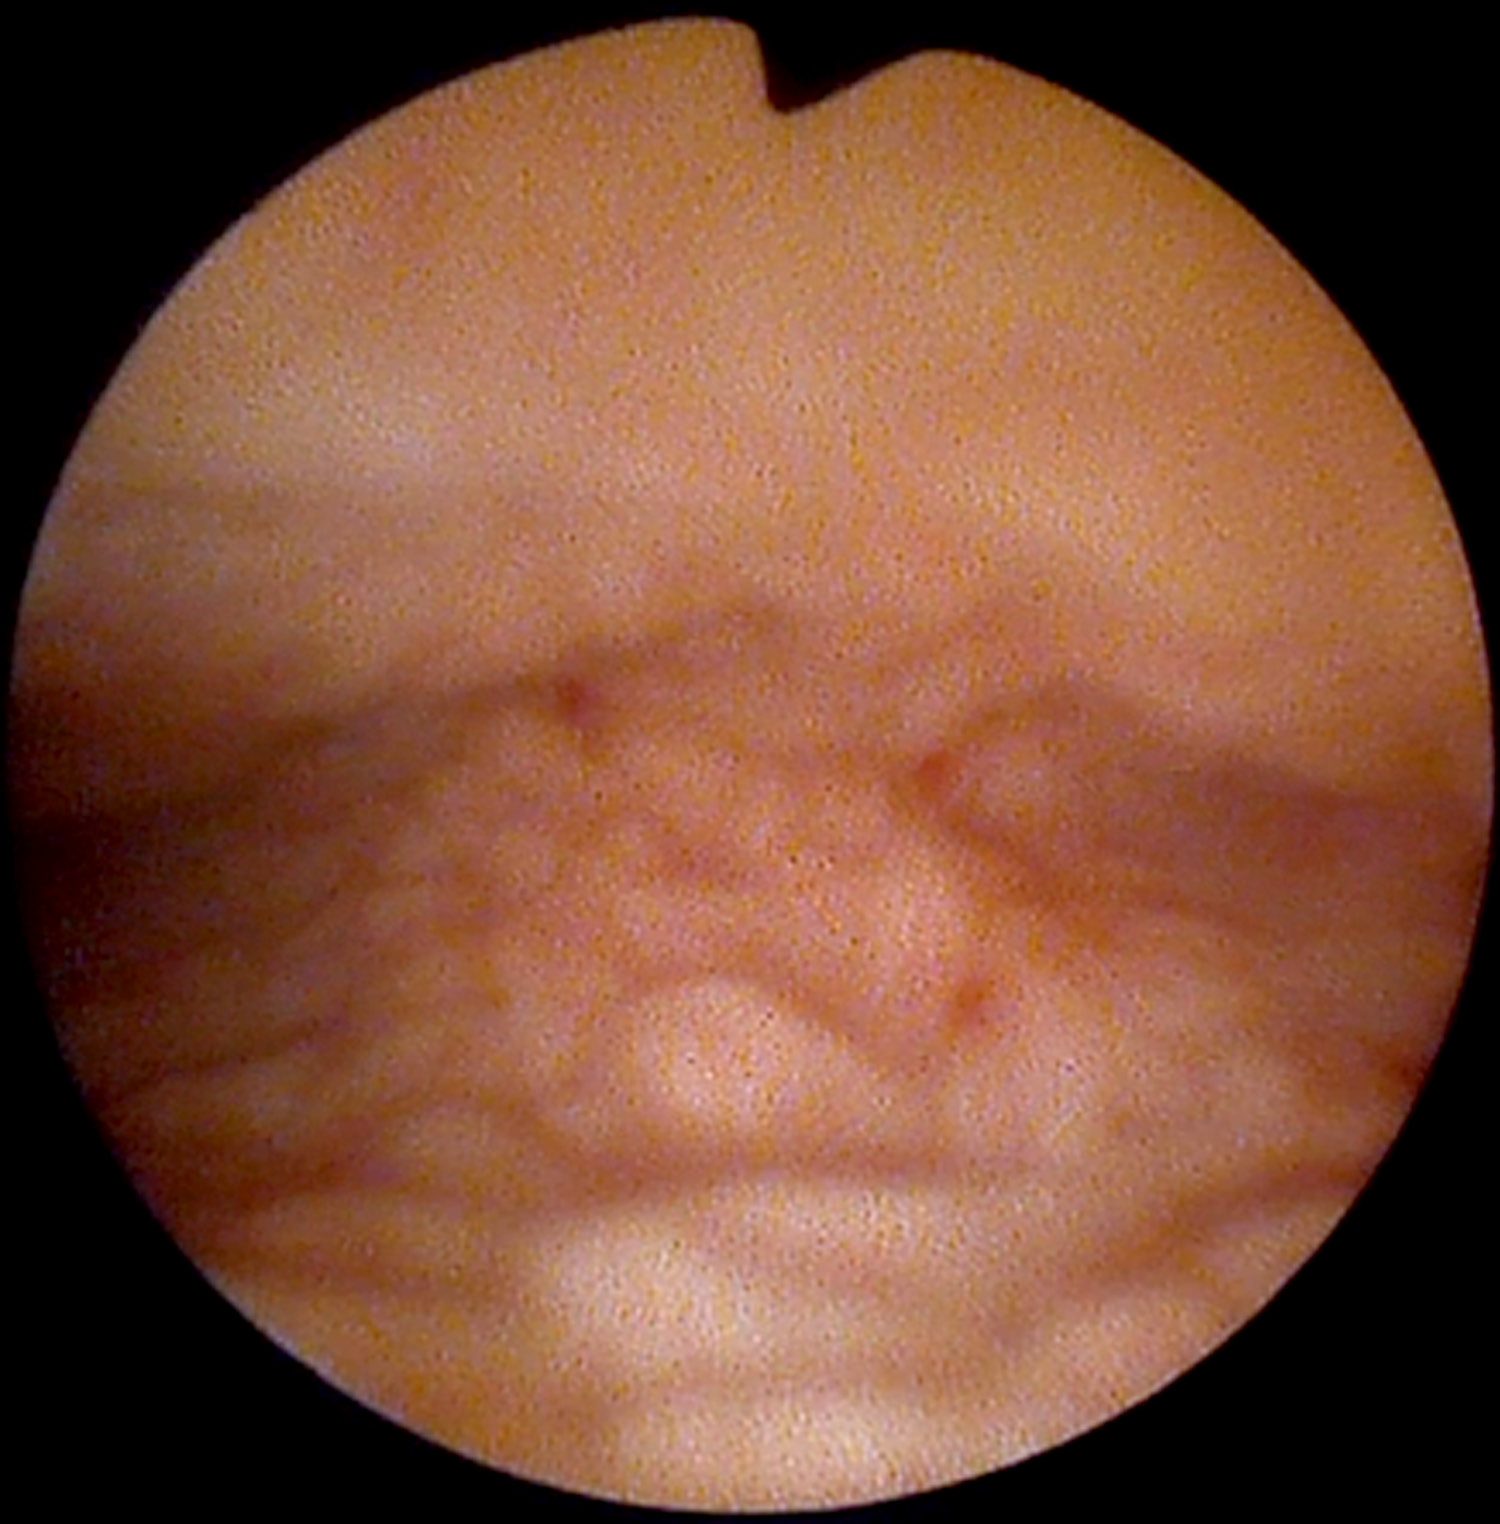

Parents contacted pediatric urologist regarding their eight-year-old daughter (twin A), who had a growth next to the external urethral meatus. The girl was referred to a pediatric surgeon. The exophytic 3 cm long structure with necrosis on top was found next to the external urethral meatus (Figure 1). There were no other abnormal findings found on medical examination. Ultrasound imaging of the kidneys and pelvic organs also showed no pathology. After obtaining informed consent from the girl parents, during general anesthesia the pediatric surgeon removed the exophytic structure next to the external urethral meatus. It was also decided to perform cystoscopy and vaginoscopy for possible changes in the bladder and vagina. Cystoscopy findings were normal. On vaginoscopy, numerous macroscopic papillomatous structures were identified on the cervix and vaginal walls (Figure 2). Vaginal biopsies were performed in areas that were affected by papillomatosis. Histopathologic examination showed a fibroepithelial polyp with a central fibrovascular core covered by squamous epithelium and vaginal squamous papillomatosis. The specimens were analyzed for human papillomavirus DNA by real-time PCR assay (Anyplex II HPV28 Detection; Seegene) and were negative for 19 high risk HPV types (16,18,26,31,33,35,39,45,51,52,53,56,58,59,66,68,69,73,82) and 9 low risk HPV types (6,11,40,42,43,44,54,61,70).

Figure 2. Vaginoscopy of twin A: papillomatous structures on vaginal walls.